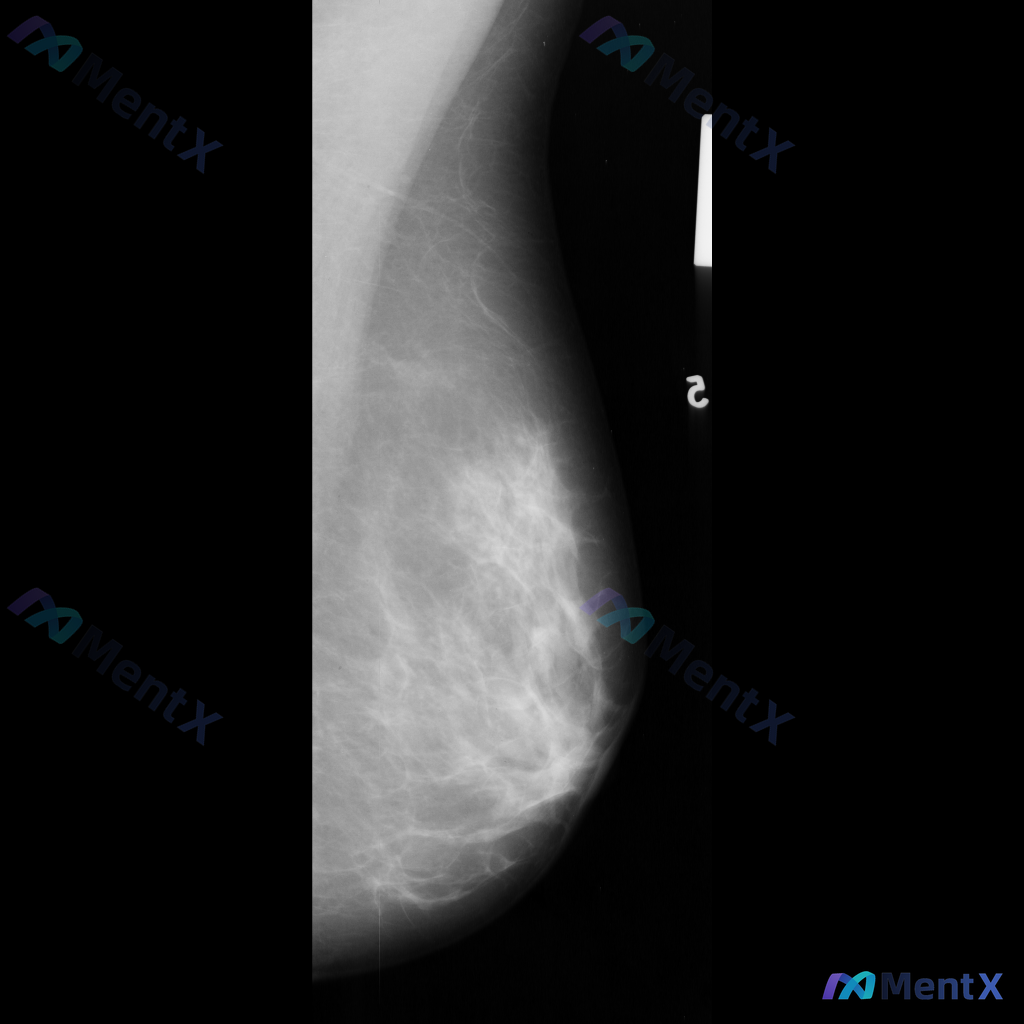

整理到一份乳腺影像的分析资料,想请大家一起讨论看看。 基本信息: - 影像类型:左侧乳腺钼靶内外斜位(MLO) 影像主要表现: 1. 左侧乳腺中上部及外侧可见局灶性结构扭曲 2. 乳腺腺体组织以纤维腺体为主,密度较高,为不均匀致密型(ACR BI-RADS C型) 3. 腺体可见多发斑片状、结节状高...

整理到一个乳腺钼靶影像的读片病例,影像上的核心表现是:不对称致密影伴结构扭曲,暂时没有看到明确的肿块描述,也未提及微钙化、脂肪影等明确良性特征。 这种表现放在一起,大家第一反应会先往哪类情况考虑?或者说,你会更优先关注哪种可能性?